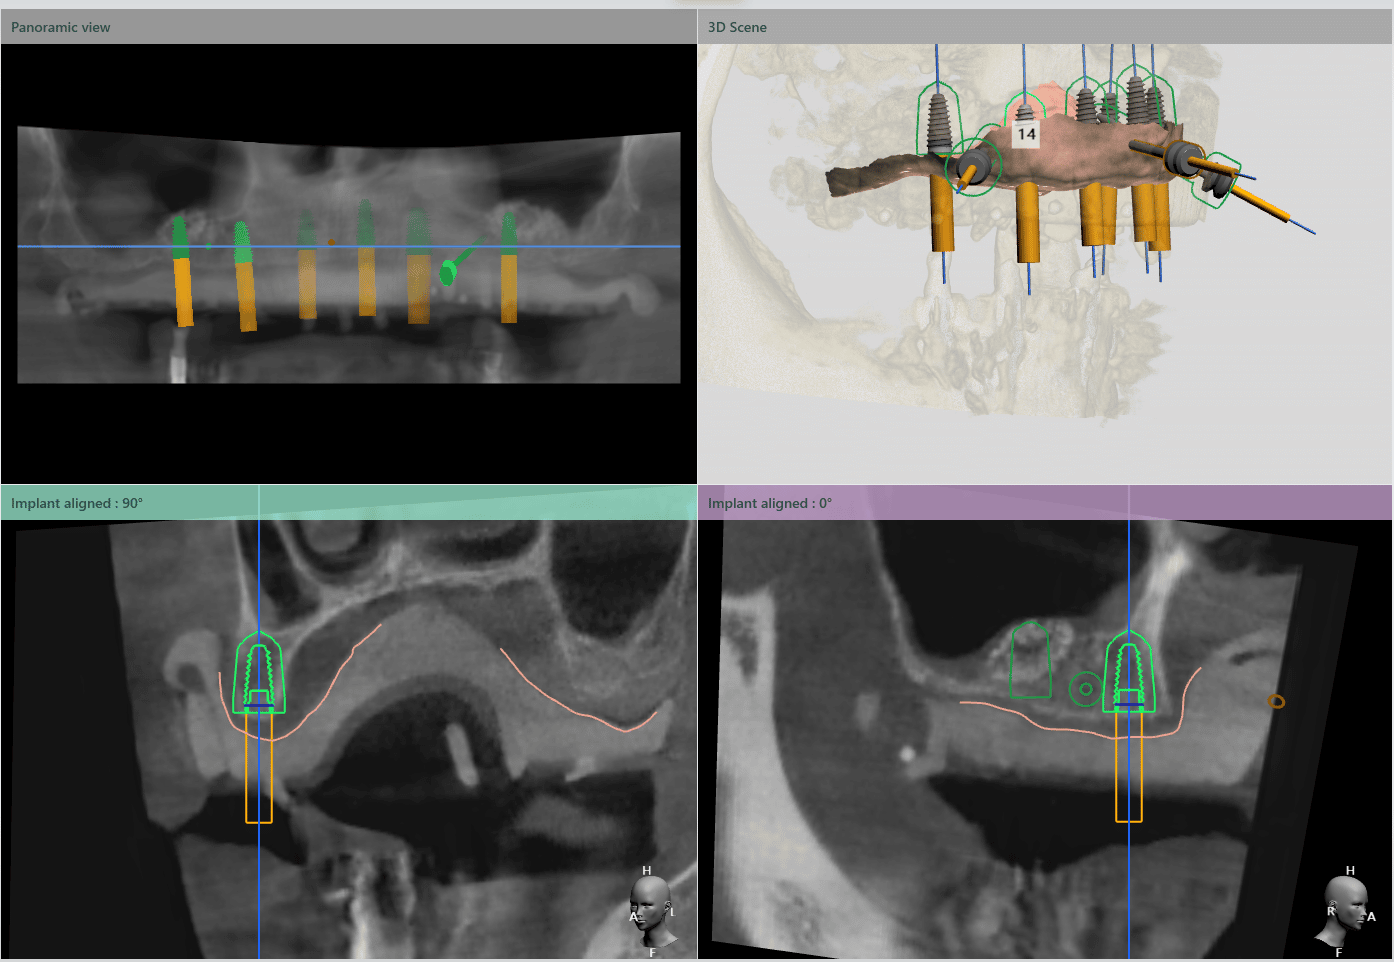

După o perioada de 6 luni, a demarat cea de a doua etapă a planului de tratament. Aceasta a constat în realizarea unui lifting sinus maxilar bilateral și inserarea a 6 implanturi cu ajutorul ghidului chirurgical DigiRay.

Medicul implantolog a recomandat pacientului inserarea implanturilor cu ajutorul ghidului chirurgical. Utilizarea șablonului chirurgical DigiRay facilitând plasarea implantului dentar în poziția ideală din punct de vedere protetic.

Medicul specialist a efactuat scanarea digitală a arcadelor pe care a trimis-o tehnicianului dentar DigiRay, împreună cu CBCT-ul pacientului.

Odată planficată și agreată poziția și axul de inserție al fiecarui implant, tehnicianul DigiRay efectuează designul șablonului chirurgical și printarea acestuia dintr-o rășină bio-compatibilă.